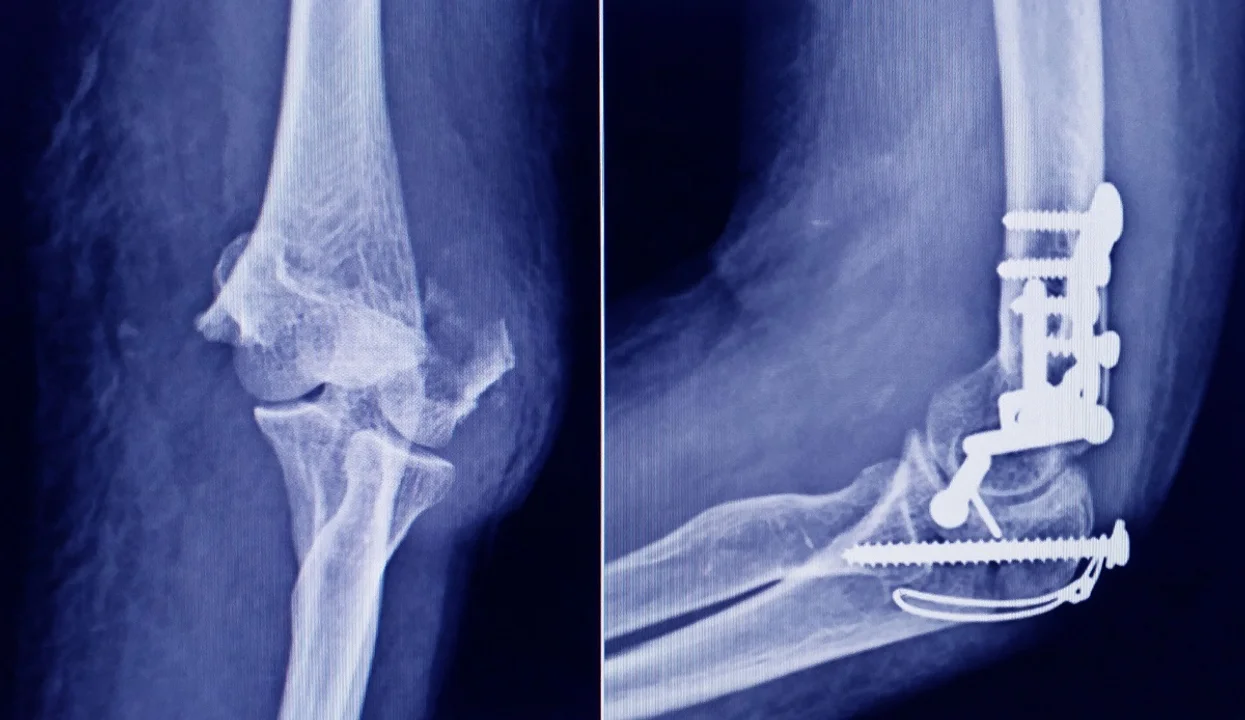

La Administración Nacional de Medicamentos, Alimentos y Tecnología Médica (ANMAT) advirtió a la población por un tornillo utilizado en cirugías traumatológicas debido a que es falso, por lo que su uso representa riesgo para la salud del paciente al que se lo implante.

Se trata de un tornillo utilizado en cirugías traumatológicas que fue detectado durante una inspección de control de mercado realizada en una ortopedia ubicada en la ciudad de San Miguel de Tucumán.

Dicho tornillo es producido por la firma Stryker Corporation, que se encuentra registrada ante ANMAT bajo el PM 594-139. Luego de la inspección, se exhibió la muestra recolectada ante la responsable técnica de dicha empresa, quien afirmó que se trataba de un producto falsificado.

Las autoridades de la ANMAT dieron a conocer las características del producto para su advertencia: STRYKER 10 mm X 28 mm – BIOABSORBABLE – ACL INTERFERENCE SCREW – REF 234-010-067 – LOT 90905.

Al tratarse de un producto falsificado, se desconoce el origen, composición, seguridad y aptitud del producto mencionado, por lo que su uso representa riesgo para la salud del paciente a quien se lo implante.